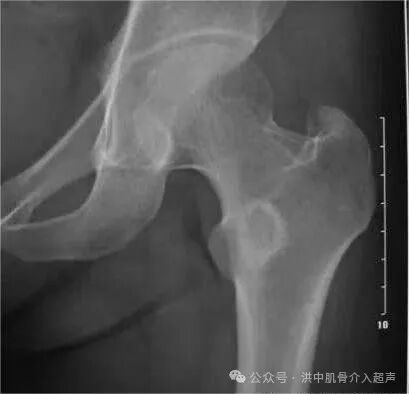

X线检查

正常髋关节超声表现